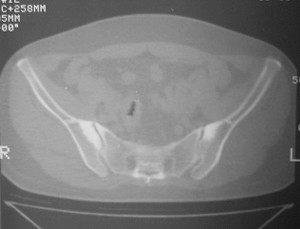

标题: CT7246: F,30岁,下腰痛,同事的片子,请老师们看看,初 [打印本页]

标题: CT7246: F,30岁,下腰痛,同事的片子,请老师们看看,初

典型的致密性髂骨炎

典型的双侧骶髂关节致密性骨炎.

致密性骨炎,好发于骶髂关节的髂骨侧的耳状面(少见部位有骶骨,耻骨联合,甚至锁骨也有报道),好发于育龄期的妇女,多对称发病

何谓髂骨致密性骨炎?髂骨致密性骨炎是发生于髂骨耳状关节部分的骨质密度增高性疾病。病因迄今不明,可能与妊娠、机械性劳损、病灶性炎症有关。本病好发于20~35岁的育龄妇女,偶见男性。

髂骨致密性骨炎的临床表现与体征:腰骶部疼痛,多呈慢性、间歇性酸痛、隐痛,可向一侧或双侧臀部及大腿后侧扩散,但不沿坐骨神经方向放射,步行、站立、负重及劳累后加重,咳嗽、打喷嚏不能使疼痛明显加重,休息后症状减轻。患者腰骶角加大,局部有压痛和肌紧张,骨盆分离和挤压试验阳性,“4”字试验阳性,化验检查多在正常范围内。x线检查,骶髂关节间隙整齐清晰,靠近骶髂关节面中的髂骨耳状关节部分骨质密度增高,呈均匀浓白边缘清晰的骨质致密带,骨小梁消失,无骨质破坏。本病应注意与早期强直性脊柱炎、骶髂关节结核相鉴别。